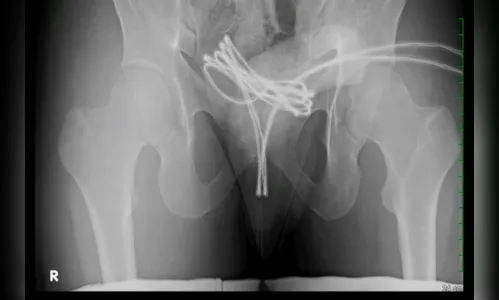

Os médicos relataram que o cabo USB estava alojado na bexiga do rapaz, o que dificultou a remoção, e tornando necessário um procedimento cirúrgico com o uso de anestesia geral, e com muito cuidado para evitar maiores danos, conseguiram remover o objeto.